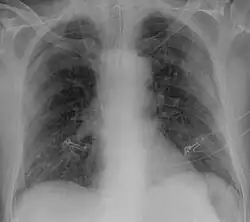

Ob ein Mensch mit dem Virus infiziert ist, lässt sich durch die Bildgebung nicht feststellen. Jedoch lassen sich bei Patienten, deren Krankheit so schwer ist, dass sie eine Lungenentzündung hervorruft, diese bildgebend nachweisen. In der Bildgebung zeigen sich im CT milchglasartige Verdickungen, wie sie auch bei anderen viralen Lungenentzündungen vorkommen.[230][231] Diese Veränderungen lassen sich aufgrund ihrer oft pleuranahen Lage auch sonographisch darstellen.[232]

Einige Wissenschaftler vertreten die Ansicht, die Diagnostik COVID-19-typischer Lungenschäden mittels Bildgebung sei der Diagnostik per RT-PCR überlegen, da die CT-Bildgebung schneller erfolgen kann und die Veränderungen zuverlässiger entdeckt werden als durch den fehleranfälligeren Abstrichtest.[215] Radiologen aus Changsha berichteten aus einer Fallserie von 167 Patienten über fünf Patienten, bei denen zum Zeitpunkt einer durch Computertomographie gesicherten Lungenentzündung die RT-PCR für das Virus negativ ausfiel und der Virusnachweis erst nach mehrmaligen Tests im Verlauf der Erkrankung gelang.[233] In Zeiten einer Epidemie kann es als Triage-Strategie bei einem gehäuften Auftreten der Patienten sinnvoll sein, Verdachtsfälle mit typischer Bildgebung auch bei negativer RT-PCR wie COVID-19-Fälle zu behandeln, um die Einleitung einer Therapie nicht zu verzögern.[231]